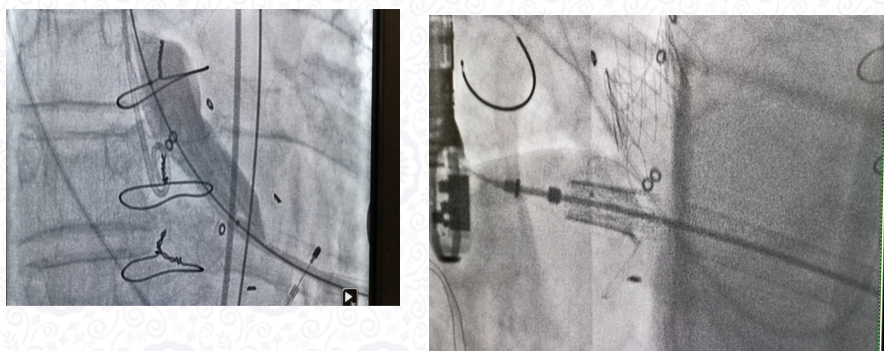

安贞医院张海波教授报告了二尖瓣生物瓣毁损介入瓣中瓣技术的创新技术发展的过程,以及临床使用中遇到的一些复杂病例。包括主动脉瓣、二尖瓣双瓣毁损的双瓣微创介入手术,主动脉瓣植入过长支架TAVI术后的二尖瓣毁损病例,主动脉瓣需要同期打断瓣环的双瓣毁损病例,二尖瓣生物瓣透视度辨识不清定位的复杂病例,总结了术中定位常见的问题和防治策略。